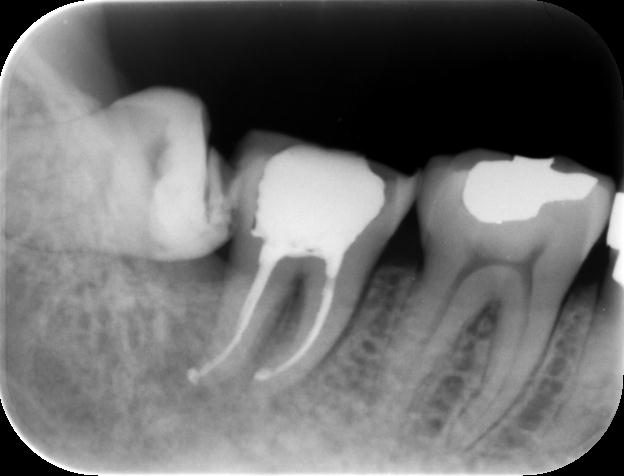

| 診断名・主な症状 | 重度叢生、狭窄歯列、前歯部交差咬合 |

左側【治療前】